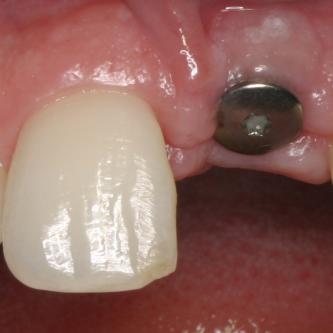

Exemple 1: Ce patient a perdu son incisive centrale gauche lors d'un accident. Un implant a été posé

Exemple 1: L'implant remplace la racine de la dent manquante

Exemple 1: L'implant s'est intégré dans l'os, une empreinte est effectuée. Le laboratoire peut réaliser la couronne en céramique.

Exemple 1: résultat final.